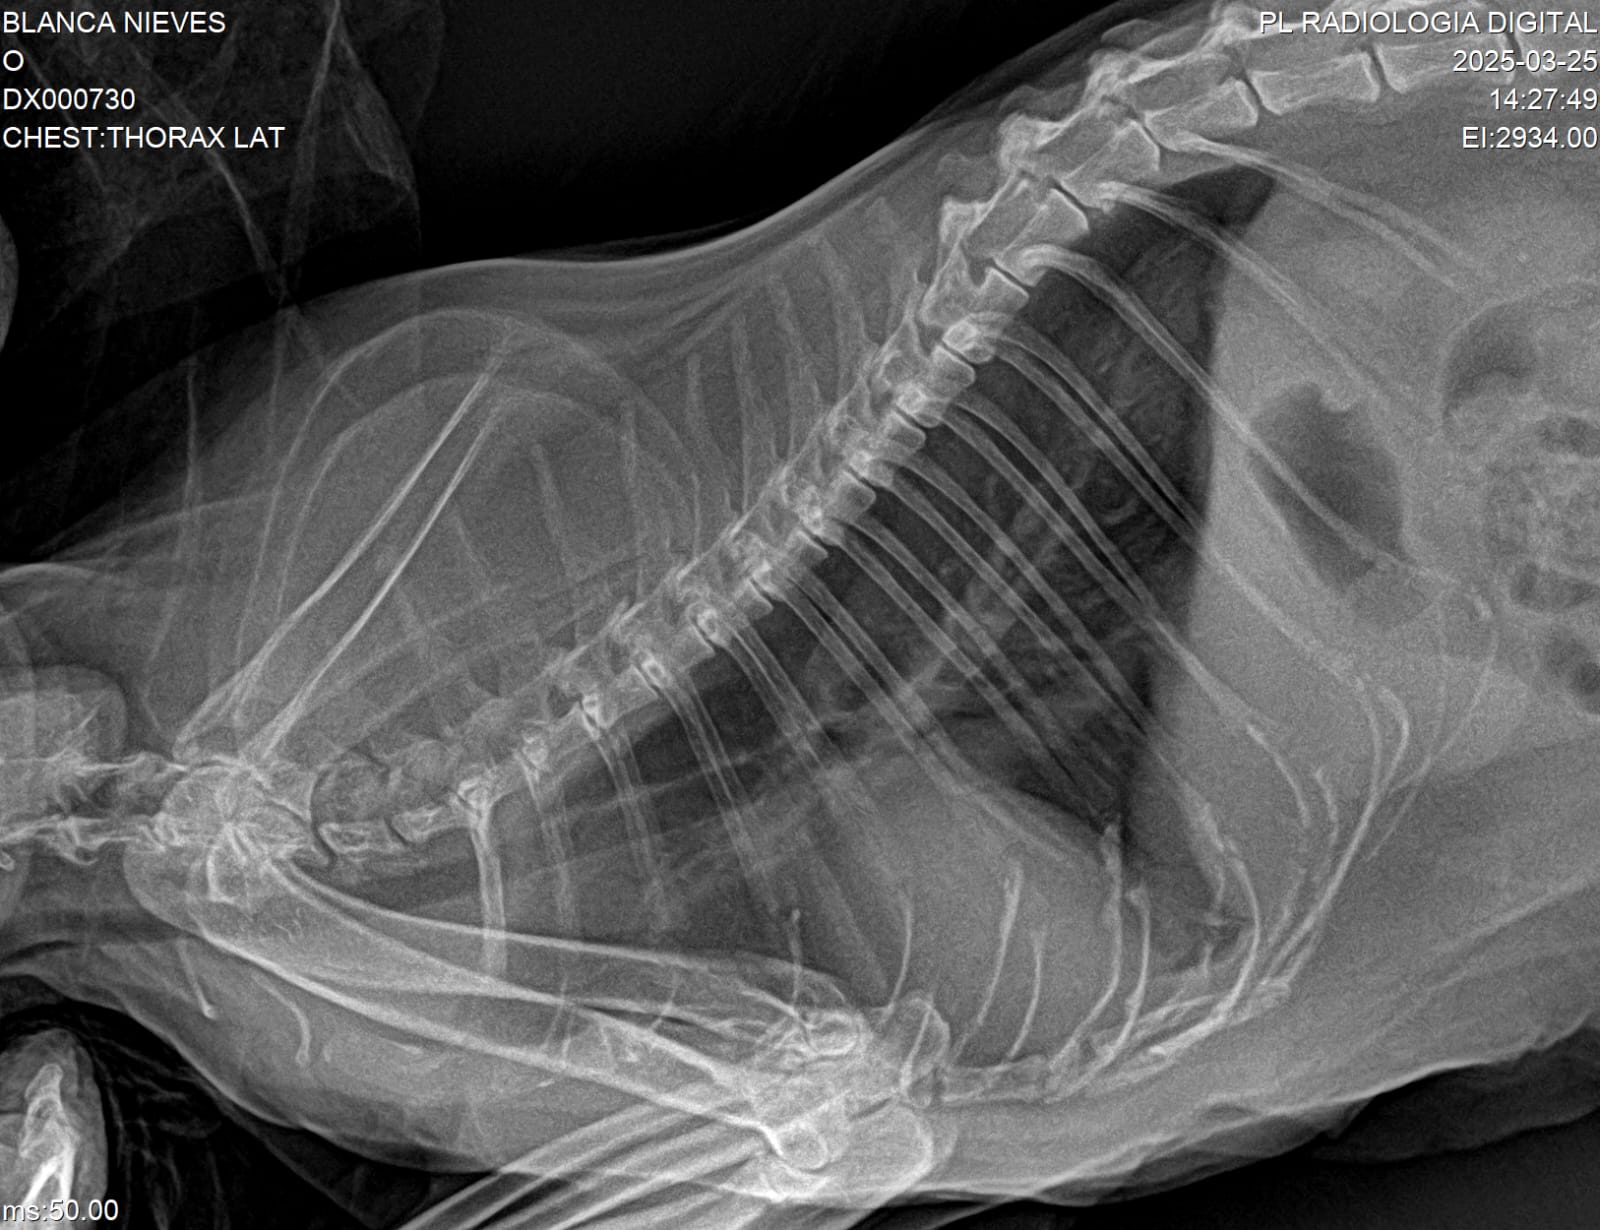

- Radiografías digitales veterinarias

- Equipos digitales portátiles con calidad de centro médico